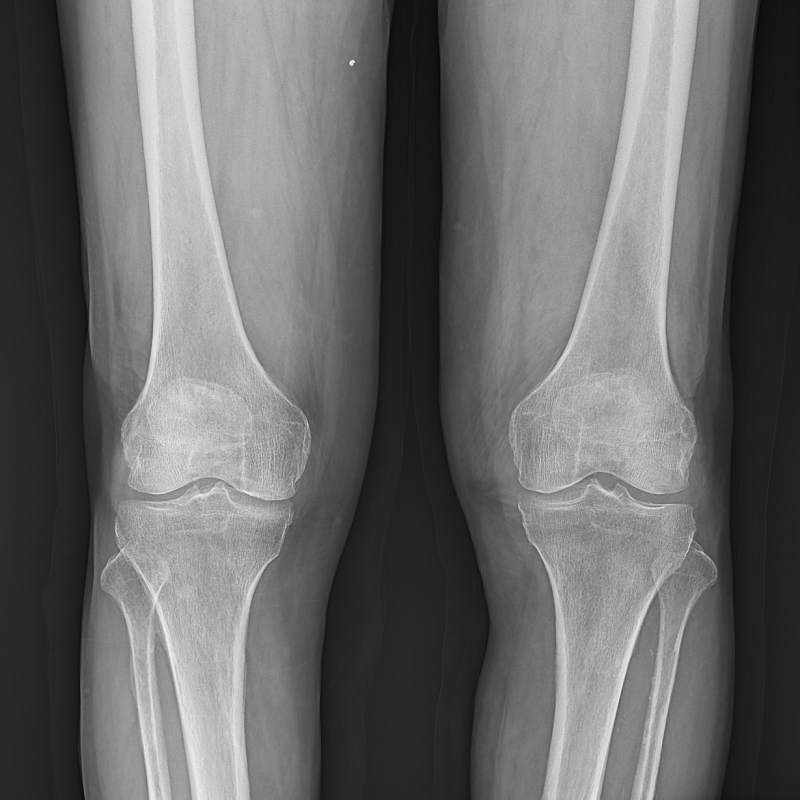

球管及胸片架可大范圍縱向移動(dòng),平板探測(cè)器中心最低離地35cm,輕松滿足膝關(guān)節(jié)、踝關(guān)節(jié)等低位攝影的要求。

● 圖像拼接

系統(tǒng)可以識(shí)別曝光圖像,無需設(shè)置識(shí)別點(diǎn)即完成精準(zhǔn)拼接,呈現(xiàn)大范圍完整影像。